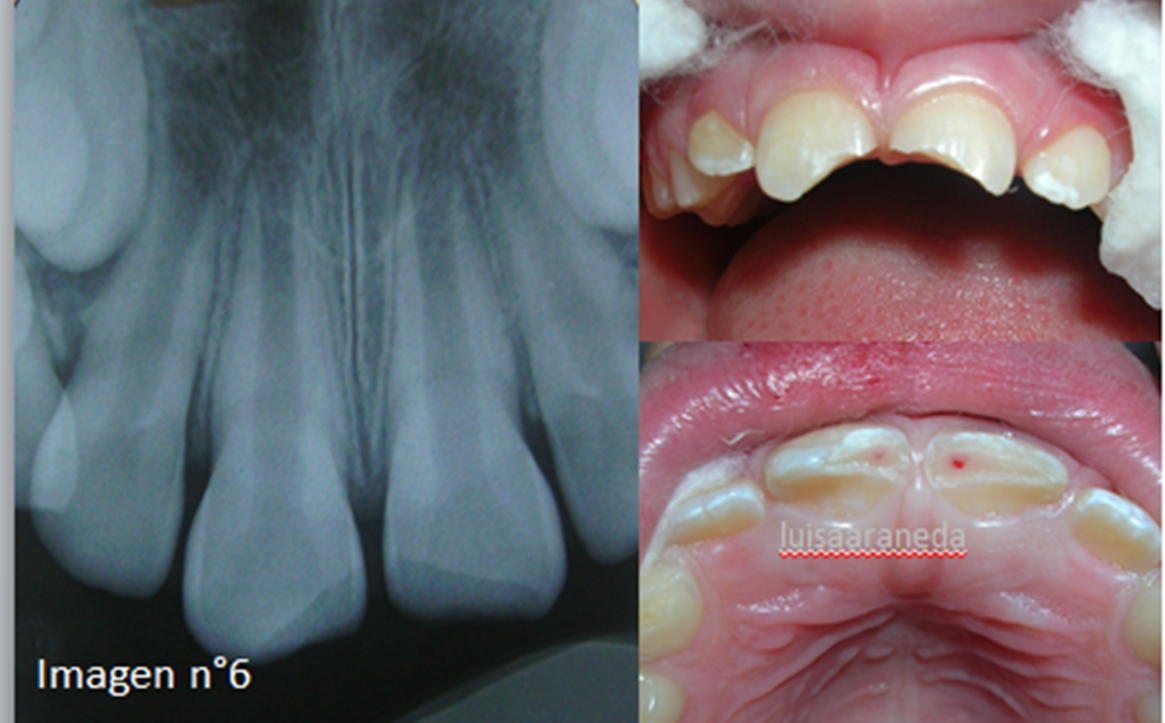

WebEfectos de la radiación en el tejido humano: efectos determinísticos (izquierda), efectos estocásticos (derecha). Los efectos estocásticos predominan en. WebEsta es la pregunta que todo mundo nos hacemos cuando nos es solicitada una radiografía dental, obviamente nos preocupa nuestra salud y queremos estar seguros de que no. WebLas radiografías consisten en un tipo de energía lanzada desde el disparador de rayos, que es capaz de atravesar los tejidos, tanto duros como blandos. Esto origina que gracias a.